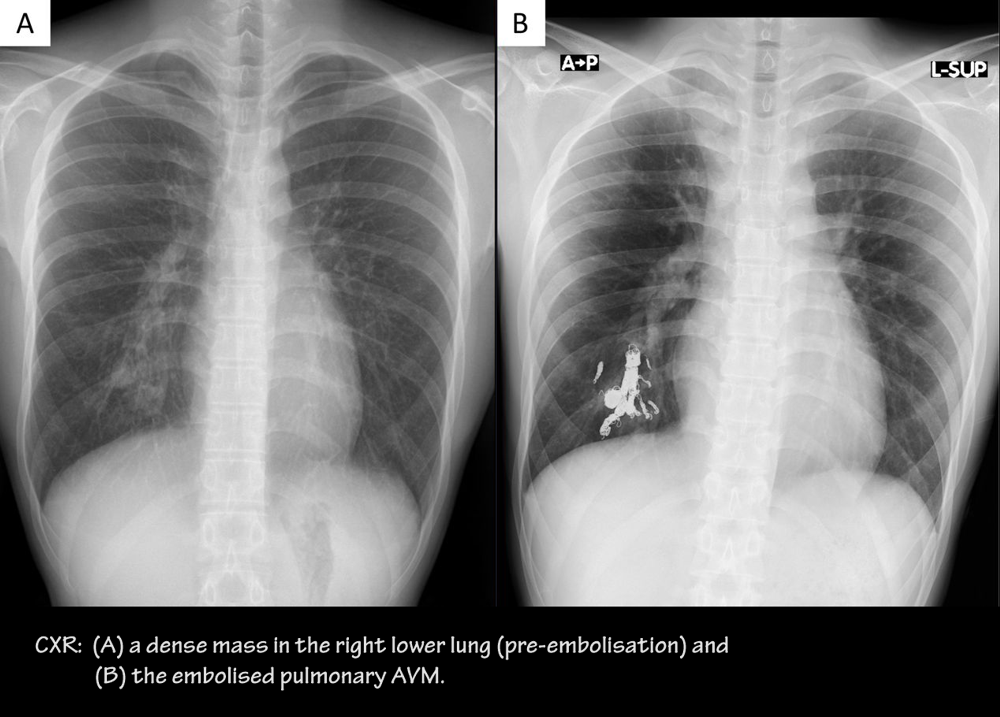

• CXR → AVMs